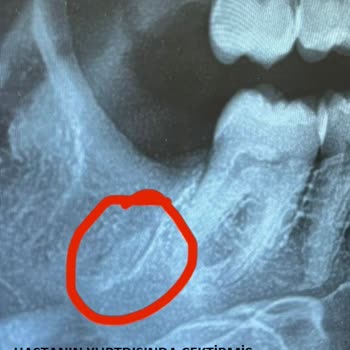

Ben 24.10.2024 Sakadent'te 20'lik dişimi çektirdim eksik tedavi uygulamasından ötürü tekrar başka bir özele gitmek zorunda kaldım. Çünkü 20lik dişin apse yapmış olmasına rağmen dikiş atılmadı İlk tedavide dikiş atılması gerekirken bir şey yapılmadığını şikayet etmek istiyorum. Hatta ve hatta çekilen...